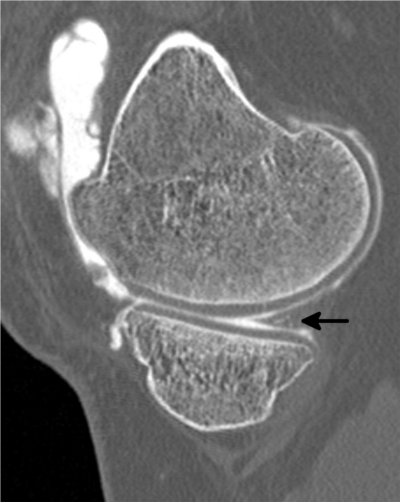

Genou

Calcifications méniscales (flèche de droite) Calcifications méniscales

Séquelles de ménisectomie (flèche de gauche)

Chondropathie fémorale (atteinte du cartilage) Fissure du ménisque interne

(flèche du haut)

Kyste méniscal (flèche du bas)